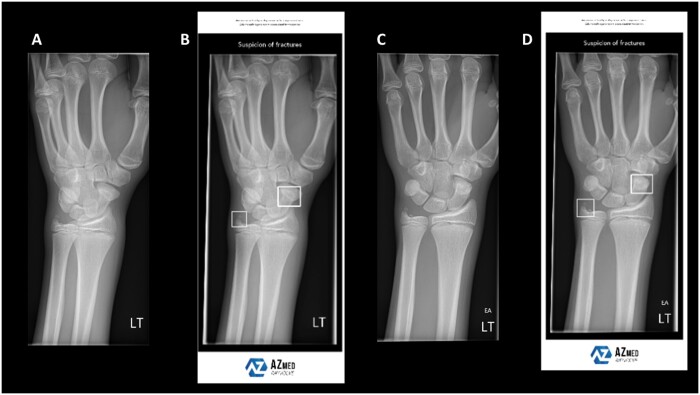

Abstract Image